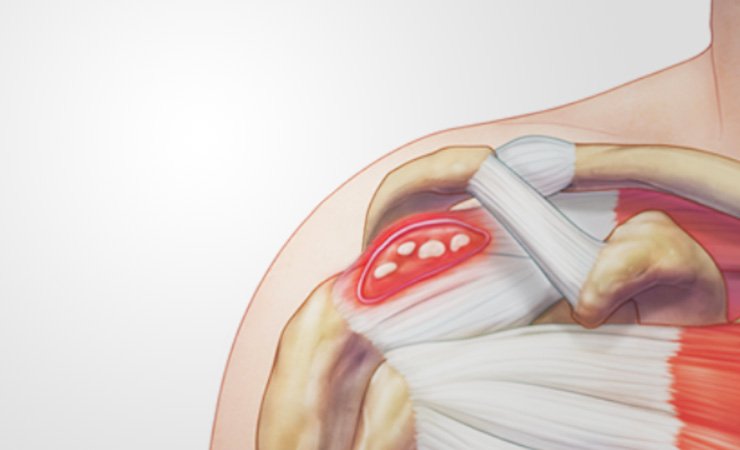

A tendinite calcária é quando cristais de cálcio se formam dentro dos tendões do ombro. Isso pode causar muita dor, especialmente na hora de levantar o braço. Não é algo incomum, muitas pessoas passam por isso, mas a boa notícia é que tem tratamento. O objetivo principal é diminuir a inflamação e aliviar essa dor chata que limita seus movimentos.

Sabe aquela dorzinha chata no ombro que parece não ir embora? Pois é, muitas vezes ela pode ser um depósito de cálcio. Isso acontece quando o cálcio, que normalmente está dissolvido, começa a se formar em pequenos cristais dentro dos tendões do ombro. Essa calcificação pode irritar o tendão e gerar bastante incômodo, especialmente com os movimentos.

A causa exata desse depósito ainda não é totalmente clara para a ciência, mas alguns fatores parecem contribuir. Problemas na circulação sanguínea local dentro do tendão e um desgaste natural com o tempo são teorias fortes. Às vezes, até mesmo um pequeno trauma pode iniciar o processo. Não é algo que acontece da noite para o dia, mas sim um desenvolvimento gradual que, quando causa dor, vira um grande problema na vida de quem sente.